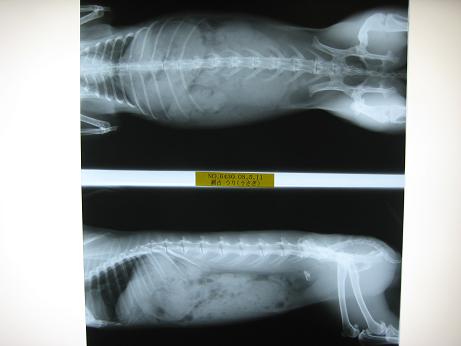

旦那『血液検査と一緒にレントゲンも取ってもらうか

』

まり『うり、よく我慢したなぁ。内蔵も骨にも異常ない。って。

血液検査の結果も以上なしで、かなりの健康さんやって

』いややぁ~